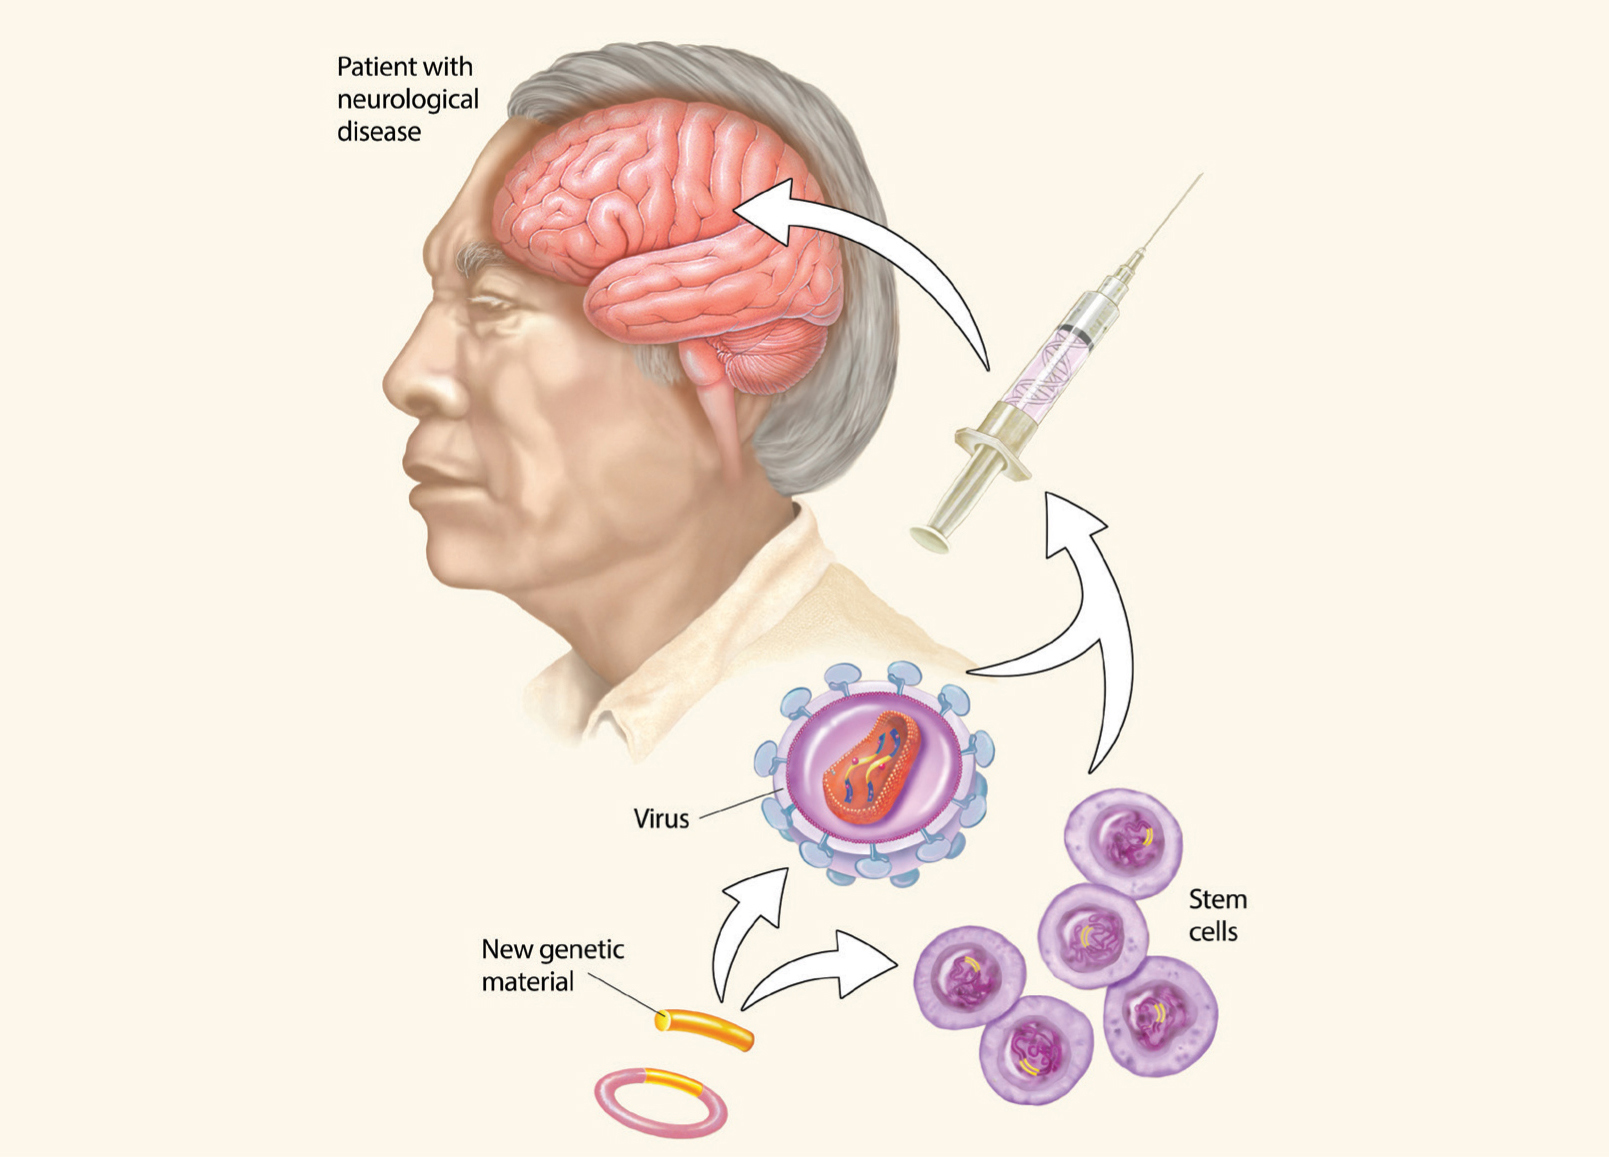

GENE REPLACEMENT

As researchers work to improve the safety and efficacy of genetic and cellular treatments, neuroscientists are finding new ways to deliver therapeutic genes into cells that need them. Designing therapies able to breach the blood-brain barrier is a challenge. Recent research has shown that small viruses with healthy genes tucked inside are able to cross the blood-brain barrier and replace faulty genes. Currently, adeno-associated virus and lentivirus seem to be the safest and most efficient vectors for gene therapy. These vectors are being used in clinical trials in patients with Parkinson’s and for some rare genetic diseases. Herpes simplex virus and adenovirus vectors have also been evaluated in early-stage human trials for treating brain tumors.

As researchers work to improve the safety and efficacy of genetic and cellular treatments, neuroscientists are finding new ways to deliver therapeutic genes into cells that need them. Designing therapies able to breach the blood-brain barrier is a challenge. Recent research has shown that small viruses with healthy genes tucked inside are able to cross the blood-brain barrier and replace faulty genes. Currently, adeno-associated virus and lentivirus seem to be the safest and most efficient vectors for gene therapy. These vectors are being used in clinical trials in patients with Parkinson’s and for some rare genetic diseases. Herpes simplex virus and adenovirus vectors have also been evaluated in early-stage human trials for treating brain tumors.

Stem cell and gene therapies hold huge potential for treating brain diseases. Therapeutic genetic material can be introduced in the brain though engineered viruses, while stem cells can be used to replace damaged or diseased cells in the brain.

CELL TRANSPLANT

To find new treatments for schizophrenia, stroke, Parkinson’s disease and other debilitating diseases, researchers around the world are turning to stem cells to study the biology of the diseases and disorders. These undifferentiated cells — from embryos or from certain adult tissues — have the remarkable potential to develop into any of the three major cell types of the brain: neurons; astrocytes, which nourish and protect neurons; and oligodendrocytes, which surround axons and enable them to conduct signals efficiently. Scientists hope that stem cells transplanted into the brain might be able to replace and repair neural cells that were lost due to disease or injury.

To find new treatments for schizophrenia, stroke, Parkinson’s disease and other debilitating diseases, researchers around the world are turning to stem cells to study the biology of the diseases and disorders. These undifferentiated cells — from embryos or from certain adult tissues — have the remarkable potential to develop into any of the three major cell types of the brain: neurons; astrocytes, which nourish and protect neurons; and oligodendrocytes, which surround axons and enable them to conduct signals efficiently. Scientists hope that stem cells transplanted into the brain might be able to replace and repair neural cells that were lost due to disease or injury.